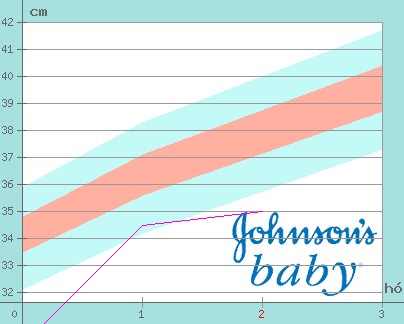

Nálunk Emese:4280gr,Adél:3960gr.Érdekes,hogy születésük óta tartják a 300 gr körüli különbséget.